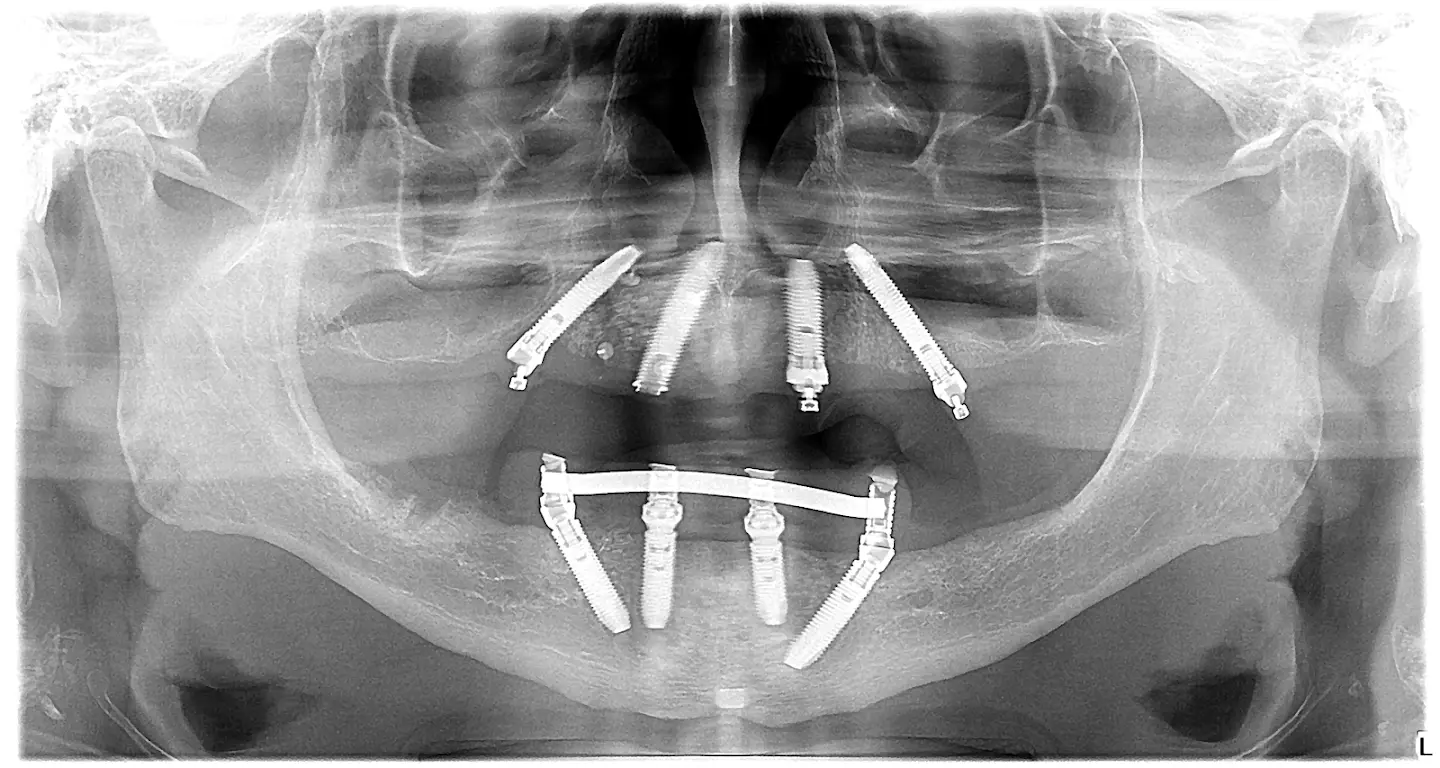

case 2 - OPT - all on 4

Reconstruction of both jaws with the ALL ON 4 method

We installed 8 dental implants - 4 in the upper jaw (Nobel speedy) and 4 (Nobel parallel cc) in the lower jaw